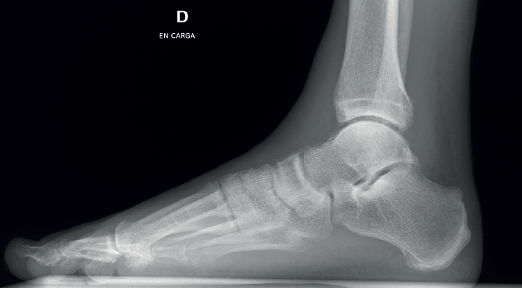

Figura 8. Radiografía lateral del tobillo con ausencia total del osteofito talar causante de la rotura completa del extensor común de los dedos.

El paciente mejoró su calidad de vida debido a que desapareció la fatiga muscular del tobillo y la pierna, sobre todo con el ejercicio, y no tenía dificultad para calzarse. Era capaz de realizar una flexión dorsal de los extensores del segundo al cuarto dedo (Figura 7) y no presentó adherencias cicatriciales en el dorso de la herida, pero sí una cicatriz queloide no sintomática. En las imágenes radiográficas observamos la desaparición del osteofito talar (Figura 8).